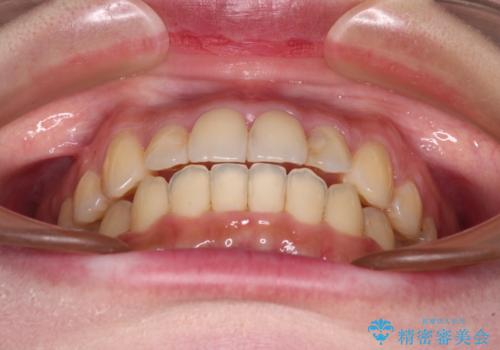

より治療を速やかに行うため、上顎右側にアンカースクリューを使用し、目標としていた1年半ほどで治療を終えることができました。